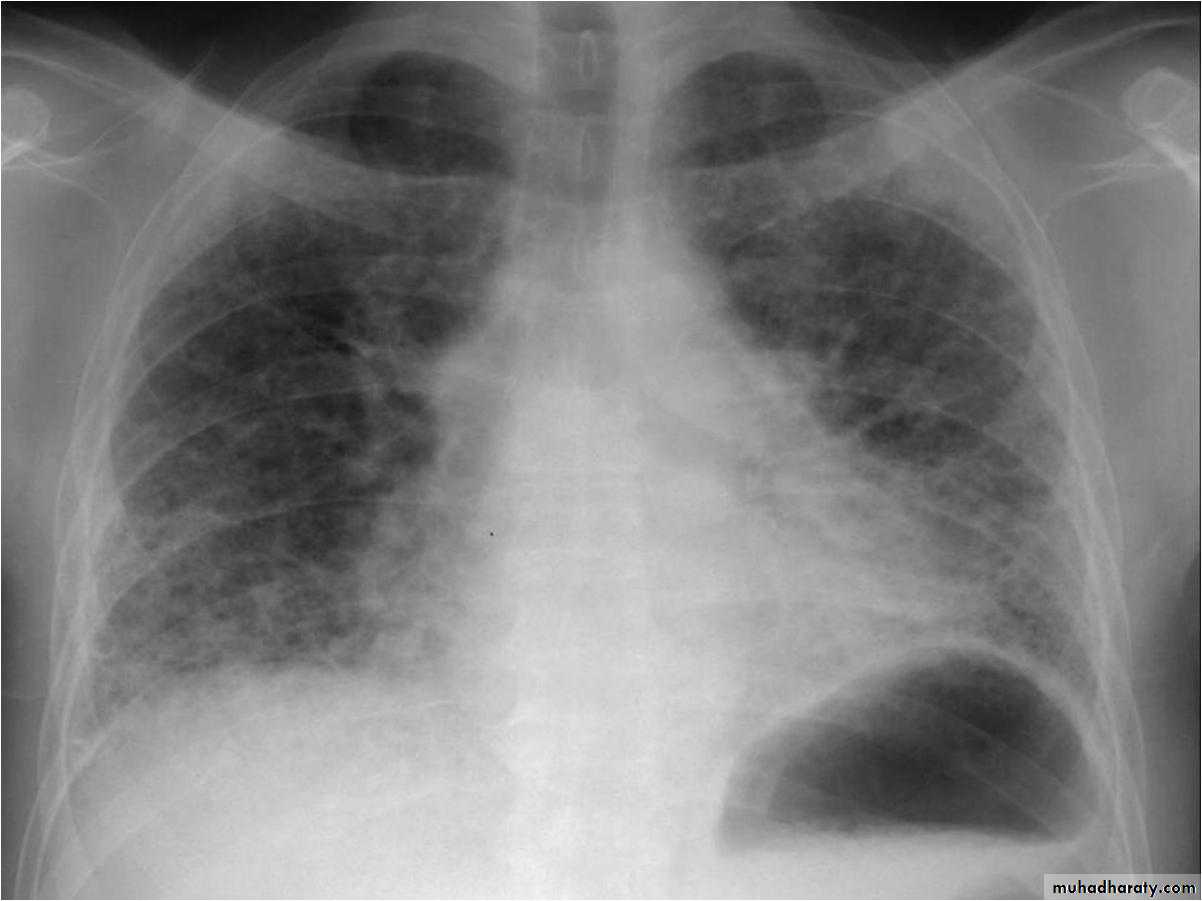

Chest X-rayLower zone shadowing

Decreased lung size

Pulmonary infeltrate